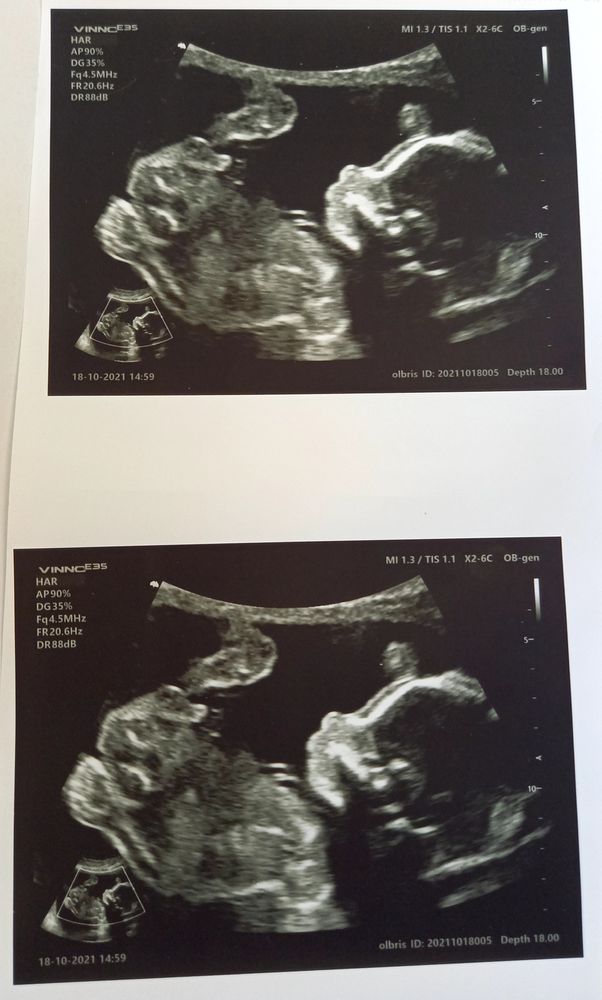

Вчера был пройден второй скриниг и теперь кружочек можно закрашивать. Итак,пол нашей дочери - сын ))))Мальчик! Муж счастлив, ведь он так хотел мальчишку, а я в растерянности. Я была на 100% уверена, что будет девчонка. Так что теория о том, что можно предугадать пол малыша по тому как проходит беременность, переходит в разряд мифов. Сейчас беременность точь в точь,как я ходила с девочкой,но,как оказалось, это не показатель. У врача переспросила несколько раз,но ответ твёрдый. Мальчишка и без вариантов) Так что мечту о бантиках и косичках можно смело отложить .

Теперь к животику можно обращаться по имени-Дмитрий Даниилович) Вот такой подарок мужу и свекру к их ДР, получился. Сначала думала помолчать эти три-четыре дня ,но по моим глазам муж и сам все понял . Пока ехали домой,то он всю дорогу смаковал слово "сын". Его эмоции стоили того,чтобы мне принять тот факт ,что у меня скоро будет два сыночка. Главное,что Димка здоров и мы его очень ждём.